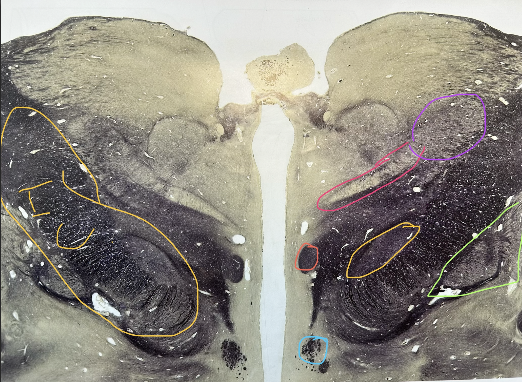

what is purple

fornix

whats in light blue

caudate nucleus

whats in dark blue

optic tract

whats in green

lentiform nucleus (putamen and globus pallidus)

whats in orange ( in green section)

putamen

whats in puple

globus pallidus, internal and external componetns

whats in pink of the left

internal capsule (corticospinal and corticobulbar axons run through here)

caudate nucleus tail

substantia nigra

whats in red ( by the tan)

subthalamic nucleus

whats in orange

whats in pink

hippocampal formation